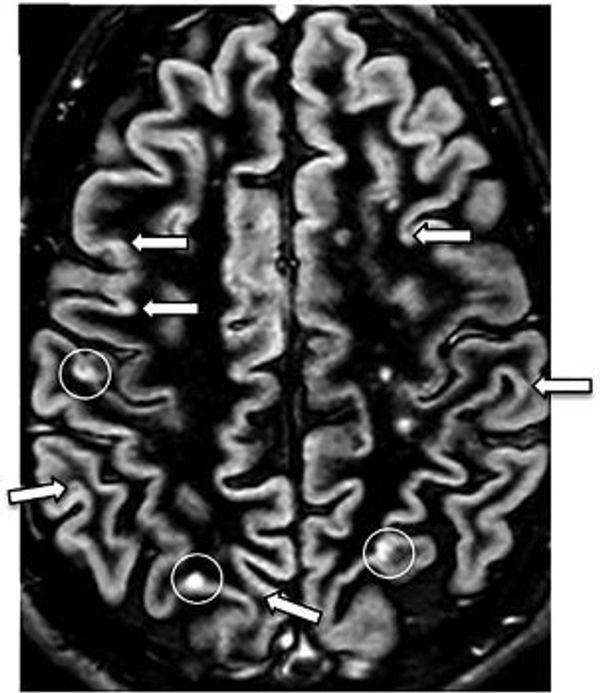

Bij Multiple sclerose wordt deze myelinelaag aangetast. Dit gebeurt door het eigen afweersysteem dat de zenuwcellen aanvalt. MS wordt daarom ook een auto-immuunziekte genoemd. In de myelinelaag ontstaan gaten wat demyelinisatie wordt genoemd. Hierdoor wordt de overdracht van signalen bemoeilijkt en uiteindelijk soms zelfs helemaal niet meer mogelijk. Het lichaam vult de ontstane gaten op met bindweefsel (het kan geen nieuw myeline meer aanmaken), waardoor er littekens ontstaan die niet meer isoleren. Dit littekenweefsel is hard en daaraan dankt de ziekte haar naam: Multiple sclerose betekent letterlijk meerdere verhardingen.